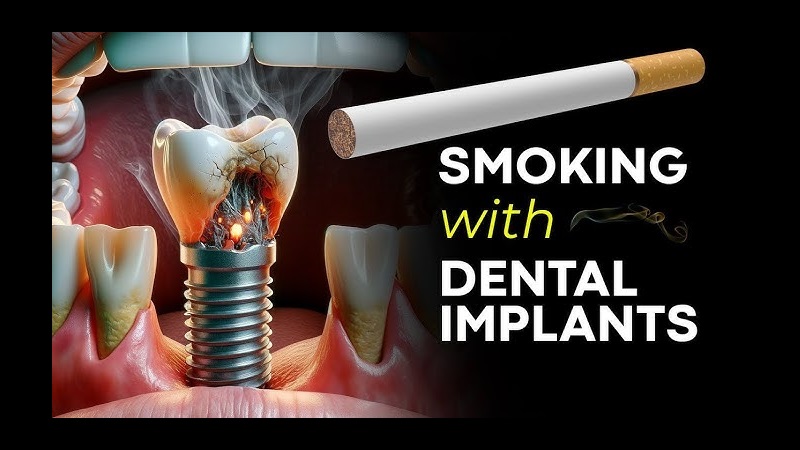

- ایمپلنت دندان اصفهان

کاشت ایمپلنت دندانی، یک سرمایهگذاری هوشمندانه برای بازگرداندن ...